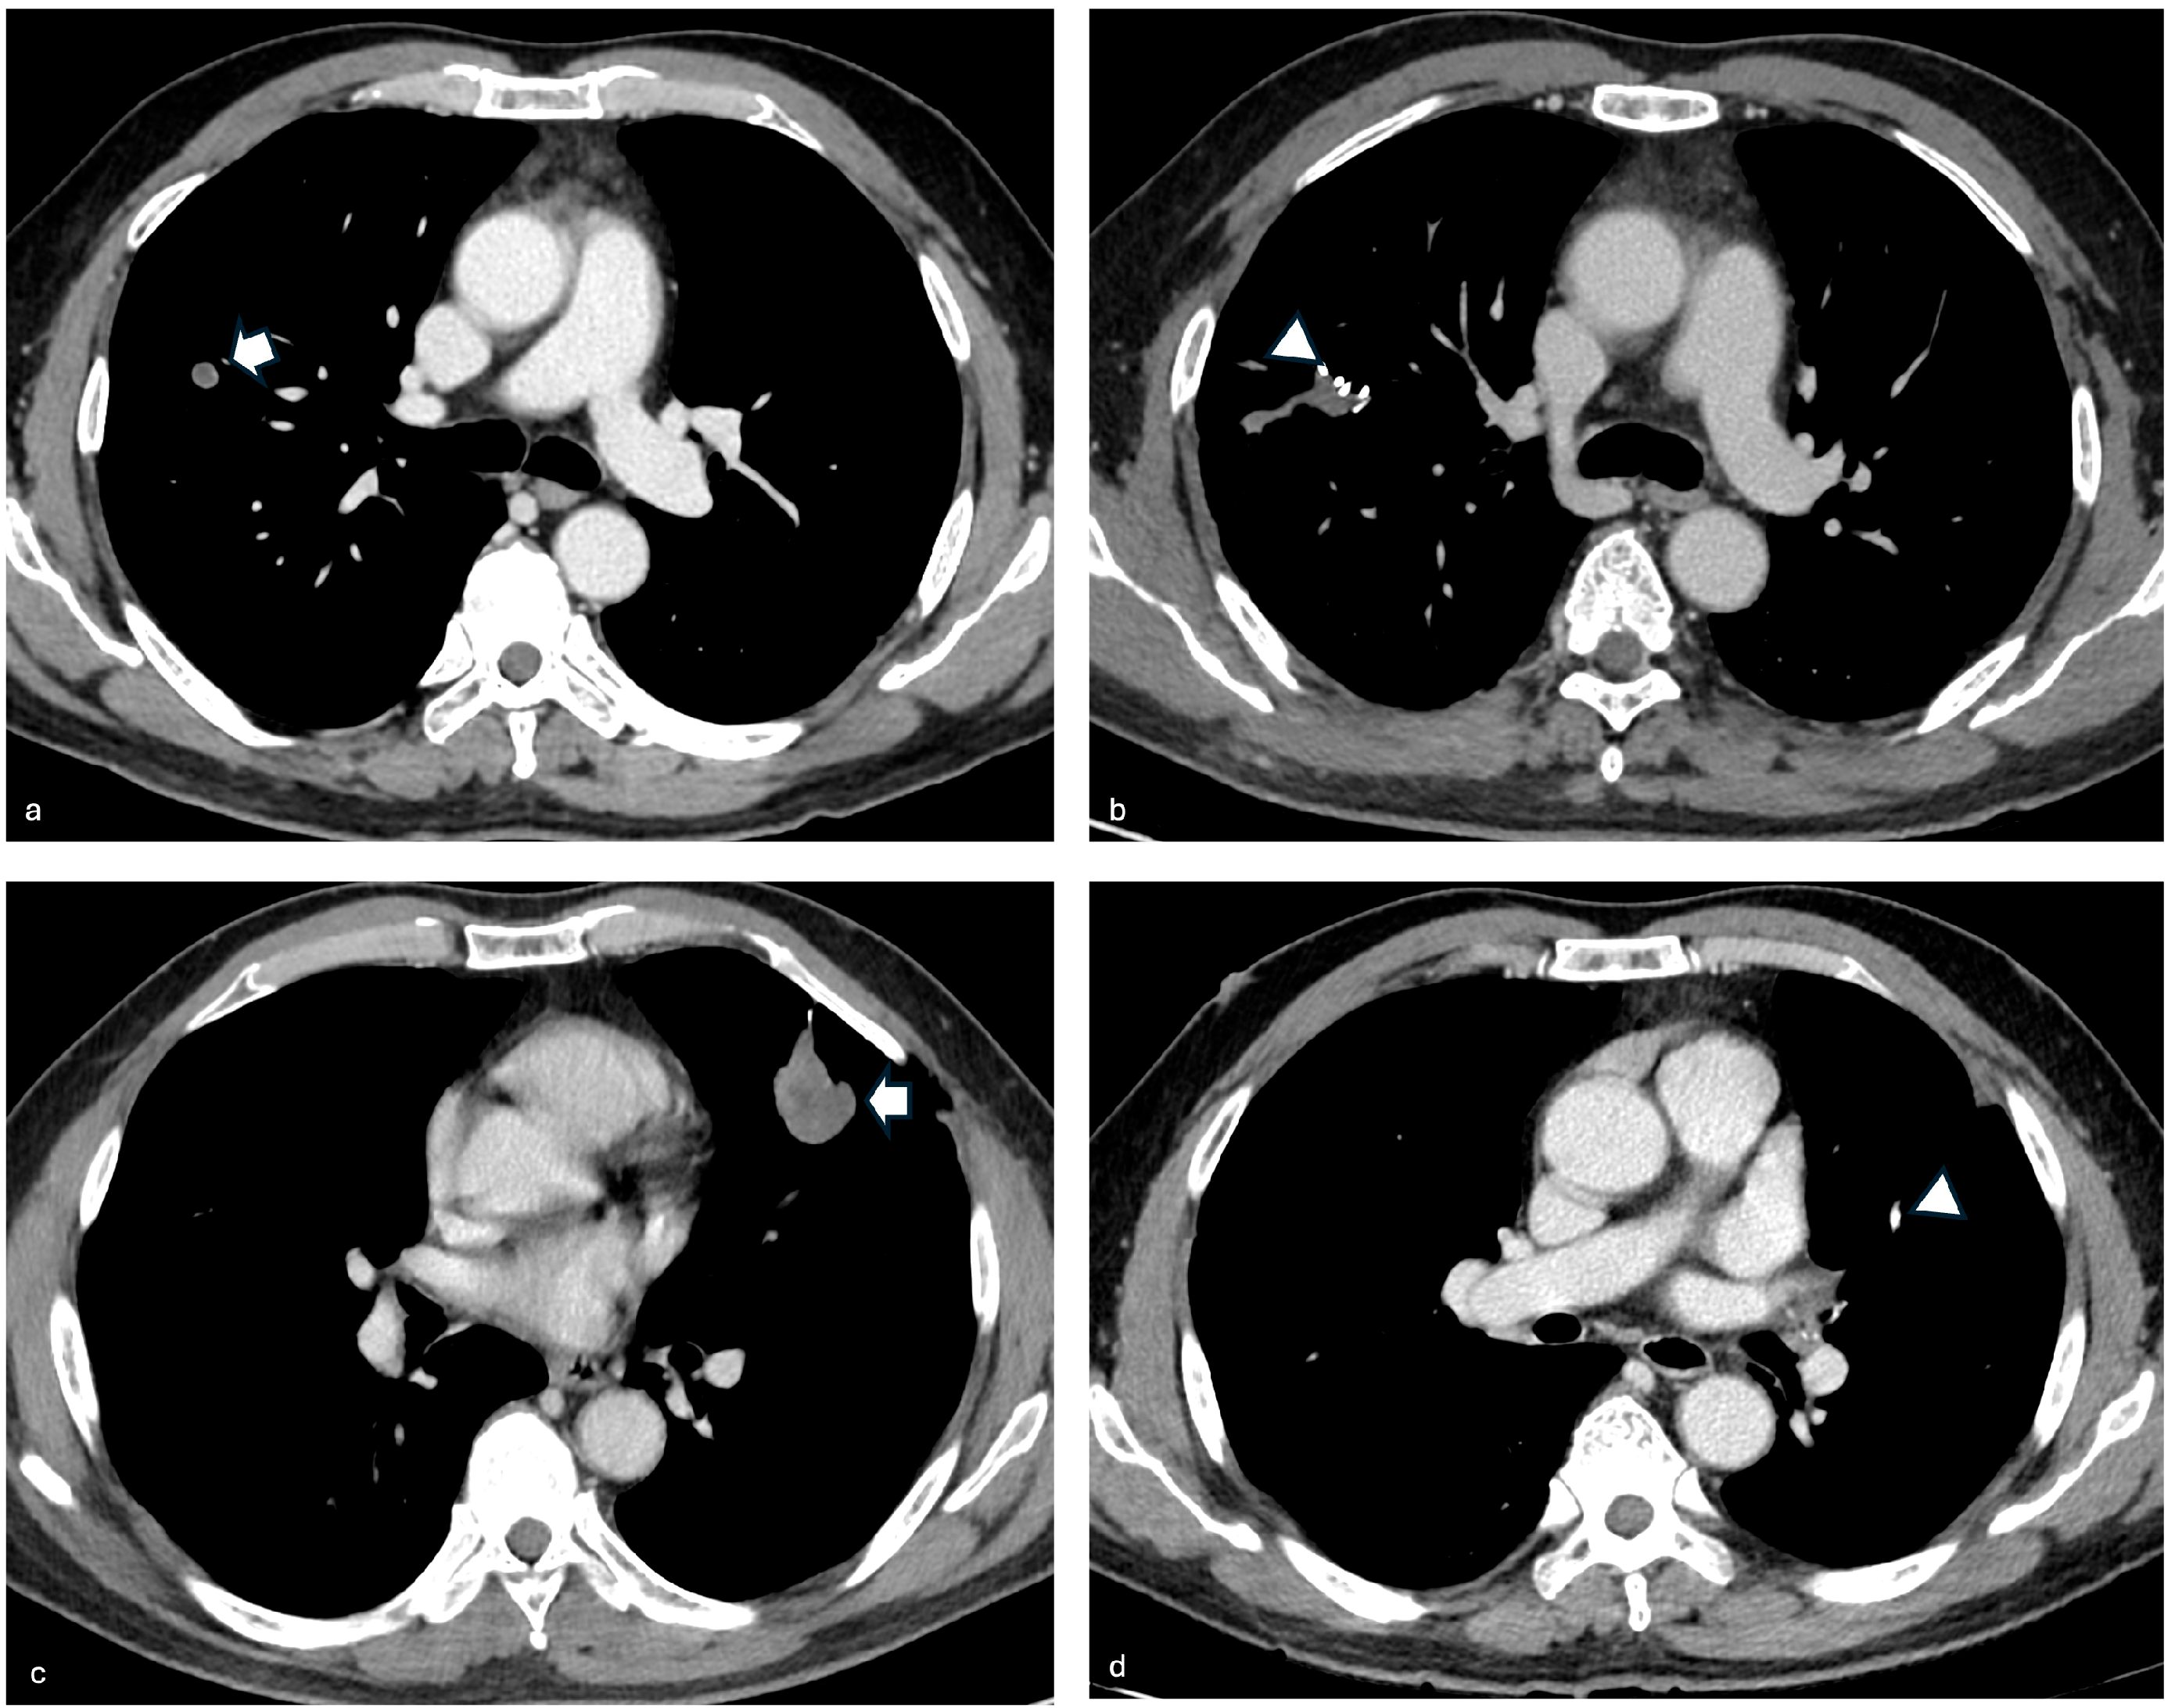

3.3. Case 3